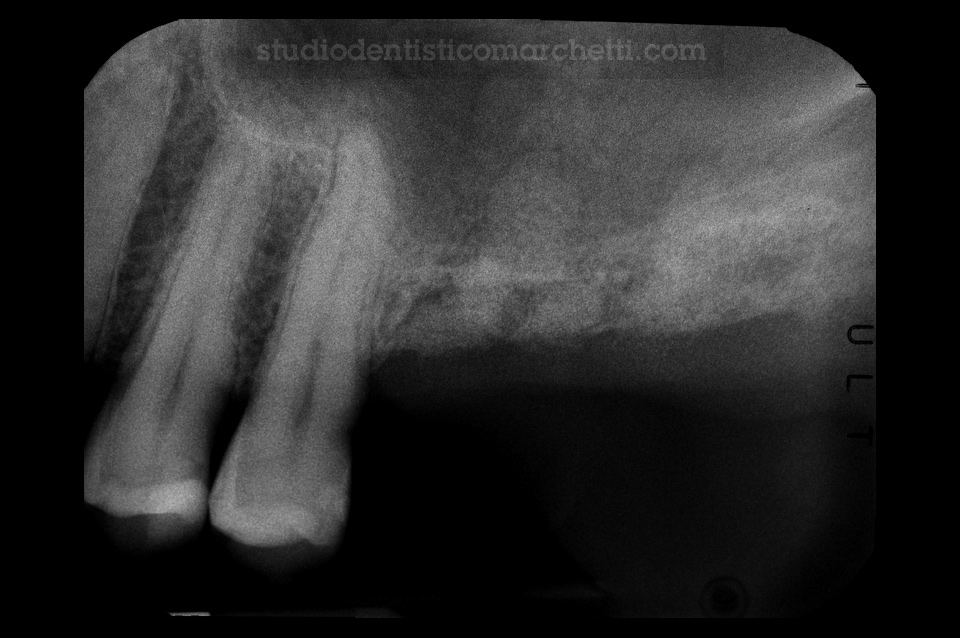

Chirurgia Orale

Estrazione di Dente del Giudizio Incluso

Chirurgia Orale

Estrazione di Dente del Giudizio Incluso

Chirurgia Orale

Estrazione di Dente del Giudizio Incluso